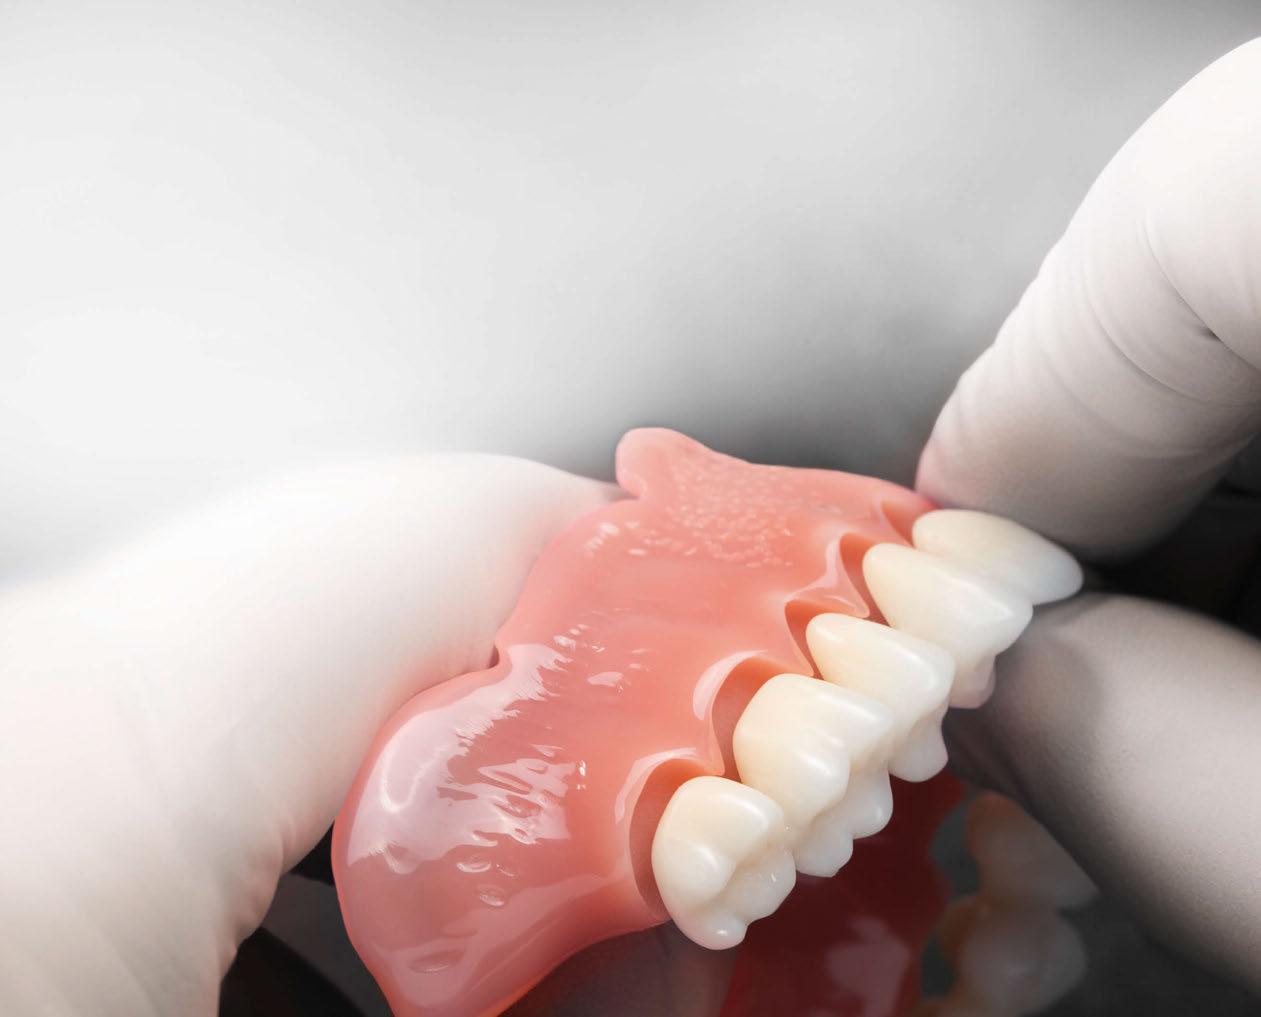

Presentamos el tratamiento rehabilitador de una paciente, realizado íntegramente en una sesión. Para este caso se ha utilizado un protocolo quirúrgico digital y guiado mediante la Plataforma de Planificación Bego Guide. Asimismo, se ha diseñado digitalmente una prótesis de carga inmediata atornillada e impresa con resina Bego VarseoSmile TriniQ®. Por lo tanto, se trata de un caso cuyo tratamiento precisa diferentes fases, pero efectuadas, todas ellas, el mismo día. De forma sencilla y cómoda para la paciente y el odontólogo, se ha obtenido una rehabilitación fija, funcional y estética. Palabras clave: Cirugía guiada, implantología oral guiada, cirugía sin colgajo, férula quirúrgica, rehabilitación fija maxilar, impresión digital, escáner intraoral, implantes dentales.

Dado que la estabilidad primaria se ha conseguido en la mayoría de los implantes, coincidiendo con la previsión propuesta en la planificación, procedemos ahora a la fase protésica. En el caso que nos ocupa, la paciente reside lejos, por lo tanto, colocamos tapones sobre los pilares transepiteliales y descansa en la sala de recuperación (Figura 30).

El procedimiento de diseño, impresión, pulido y cementación de aditamentos consume

aproximadamente una hora y media. Usamos resina Bego VarseoSmile TriniQ® para puentes definitivos. Aunque en este caso la vamos a usar para confeccionar unas prótesis fijas atornilladas provisionales de larga duración, dado al aumento de dimensión vertical que vamos a realizar a la paciente, de esta forma obtendremos una neuroprogramación de la ATM reinstaurando una Dimensión Vertical apropiada y mejorando la estética facial de la paciente. Excluimos de la carga aquellos implantes que no obtuvieron una estabilidad primaria superior a 35 N/ cm2. El material permite la realización de una carga inmediata en material definitivo en puentes (Figuras 31 a 38).

Decidimos realizar una prótesis impresa ya que permite trabajar bajo el concepto «chairside», es decir, de ser necesario, desde la misma consulta, con el paciente en ella (en nuestro caso descansando desde la sala de recuperación), sin necesidad de intermediarios, se puede confeccionar una prótesis completamente personalizada con una adaptación y pasividad total. Asimismo parece que la impresión 3D produce coronas permanentes con una precisión dimensional superior (12).